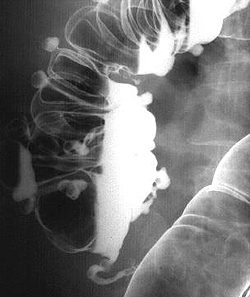

(а) На рентгенограмме ободочной кишки визуализируются утолщенные складки, наличие которых обусловлено утолщением циркулярной мышцы (стрелки) — вторичные изменения по отношению к укорочению и утолщению продольной ленты ободочной кишки. Дивертикулы (указатели) представляют собой мешковидные выпячивания стенки кишки между волокнами циркулярного мышечного слоя.

(Справа) На рентгенограмме, выполненной при ирригоскопии с двойным контрастированием, определяется дисторсия просвета ободочной кишки. Выбухающие участки В представляют собой дивертикулы, в то время как неравномерно распределенные вдавления стенки В отражают изменения, обусловленные гипертрофией циркулярного мышечного слоя.

При ирригоскопии, данными, свидетельствующими о дивертикулите, являются: частичная обструкция ободочной кишки, протяженная переходная зона, сохранность складок слизистой оболочки и наличие дивертикула (Laufer, 2008).